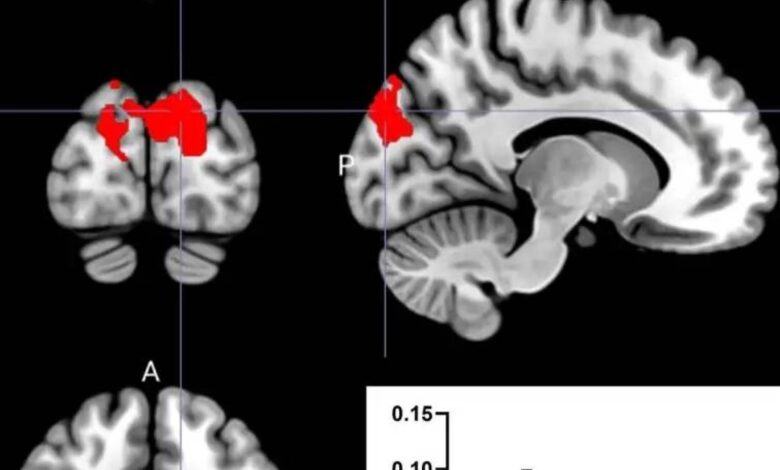

استخدم الباحثون الرنين المغناطيسي (MRI)، اختبارات وظائف الدماغ، واستبيانات لتقييم التأثيرات على الدماغ. وأظهرت النتائج اختلافات واضحة في الاتصال الوظيفي للدماغ بناءً على شكل تناول البروبيوتيك، مما يعزز فهم دور محور الأمعاء-الدماغ (Gut-Brain Axis) في الشيخوخة الصحية.